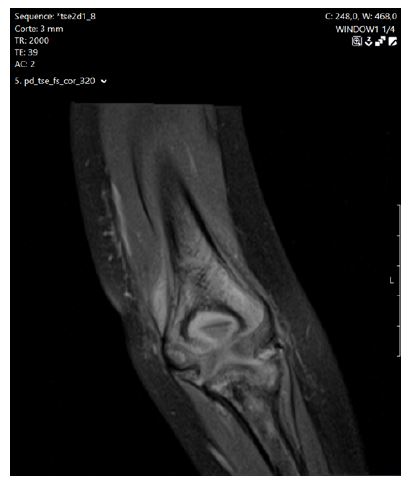

One week later, the girl was re-evaluated in the ED for recurrence of symptoms (pain and functional limitation in the left elbow). Laboratory study revealed persistent neutropenia (leukocytes 3,400/uL; neutrophils 720/uL), and ultrasonography showed persistent joint effusion in the left elbow. Magnetic resonance imaging was performed and suggested osteomyelitis of the distal humerus with endomedullary abscess collection, cortical rupture, and extension into the joint cavity (Figure 4). A new course of parenteral antibiotics (flucloxacillin) was started and subsequently escalated to piperacillin-tazobactam. Two doses of granulocyte colony-stimulating factor (G-CSF) were administered for severe neutropenia, with very poor tolerability (severe bone pain) and no documented response. A bone biopsy of the left distal humerus was performed and was consistent with chronic osteomyelitis without identification of microorganisms. Bone marrow analysis was performed with bilateral bone marrow biopsy described as normal with no maturation abnormalities or neoplasm/foreign cell infiltration. However, the simultaneous bone marrow aspirate revealed the presence of 15% abnormal immature lymphoid cells and approximately 70% lymphoblastic cells on the contralateral side. Because of persistent severe neutropenia and new symptoms (contralateral upper limb pain with edema and functional limitation), a repeat bone marrow biopsy and aspirate was performed two weeks after the first. The diagnosis of B-cell acute lymphoblastic leukemia was clearly established by immunophenotyping of the small sample obtained by aspiration (dry tap). It was also evident from the massive infiltration of B-lymphoblasts in the bone marrow trephine fragment, which showed only residual normal hematopoiesis and increased reticullin infiltration. Leukemia treatment was initiated through the ALLTogether1 protocol. Two years after diagnosis, the girl is in complete remission on anti-leukemic therapy.

Figure 3 Osteoarticular scintigraphy with Tc99m showing a lesion at the distal end of the left humerus.